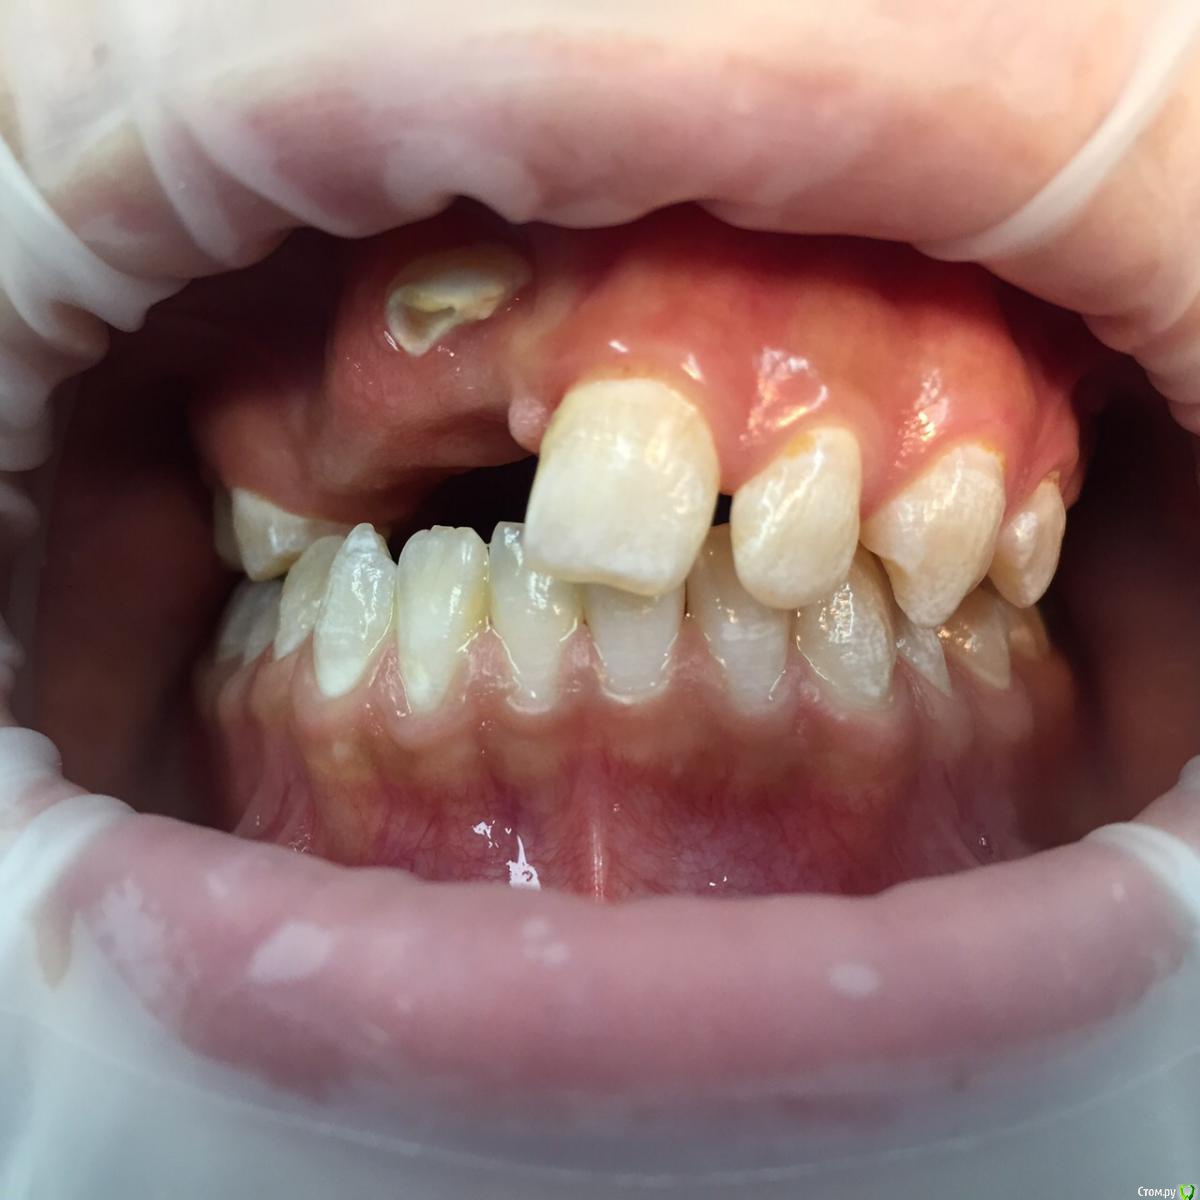

Солнечный СВЕТ Опубликовано 15 февраля, 2015 Поделиться Опубликовано 15 февраля, 2015 Девочка 14 лет, зубы не прорезались,у девочки уже комплекс,родители тоже не знают что делать,готовы ехать в другой город только бы помог кто нибудь,сейчас носит чсп,какие возможны варианты лечения и куда можно обратиться чтобы смогли помочь?!?!?!?! Ссылка на комментарий

SDC Опубликовано 15 февраля, 2015 Поделиться Опубликовано 15 февраля, 2015 (изменено) А почему не начато ортолечение с вытяжением не прорезавшихся?Наша ортодонт несколько кейсов с непрорезавшимися клыками-премолярами сейчас ведет и как то обыденно все проходит. Изменено 15 февраля, 2015 пользователем SDC Ссылка на комментарий

SDC Опубликовано 15 февраля, 2015 Поделиться Опубликовано 15 февраля, 2015 (изменено) Ориентировочный план: 1-е посещение : консультация с КТ и слепками (принятие решения о том в какой последовательности вытягивать зубы) скорее всего, возможно по моделям и КТ без пациентки. 2-е посещение: начало лечения, будет начинаться с раскрытия и диагностического вытягивания ретинированных зубов (последовательность будет ясна после диагностики КТ). Аппарат для диагностического вытягивания: скорее всего кантилевер. В среднем плановые визиты на 1м этапе : 1-е с периодичностью в 1,5-2 месяца. После положительной динамики выдвижения ретинированных зубов, переход на полную брекет-систему. Изменено 15 февраля, 2015 пользователем SDC Ссылка на комментарий

krokomot Опубликовано 28 февраля, 2015 Поделиться Опубликовано 28 февраля, 2015 (изменено) ничего подобно не произойдет если все делать правильно, но возможно, что головоломка и не сложится, хотя складывались и не такиеобязательно :наладить гигиену,сделать модели и ктфиксация системывытяжениеПорядок время и последовательность определяться после изучения кт и моделей. Изменено 28 февраля, 2015 пользователем krokomot 1 Ссылка на комментарий